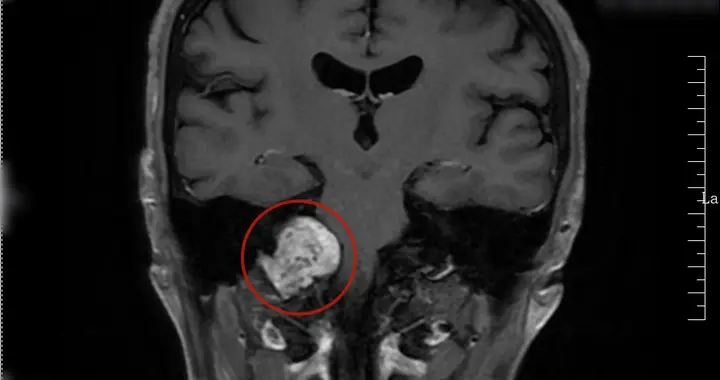

颅内肿瘤“蛰伏”10余年长到网球大小 武大人民医院多学科联手揪出精神障碍背后的“隐形炸弹”